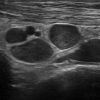

Viêm ruột

» Thông tin: Nữ giới – 55 tuổi.

» Lâm sàng: Tiêu chảy.